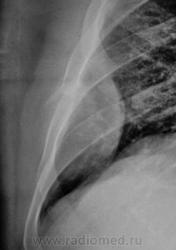

Контроль после флюолрографии.  Мезотелиома или что-то другое?

Скорее деструкция 6 ребра с мягкотканным компонентом

Да, деструкция ребра видна хорошо, да и сиротские фрагменты (костные) тоже. "Мягкотканный компонент", прямо богатейший.

Мезателиома отпадает, данную картину мы бы не увидели за счет жидкости плевральной полости, а вот саркому Юинга бокового отрезка ребра я бы предположил.

Может и Юинг, хотя мне кажется староват, а может: мтс, плазмоцитома, хондросаркома и т.д. В смысле, и все остальные опухоли костей. Потому надо брать биопсию, благо, в этом месте не сложно.

Бок, конечно, руководствуясь стандартом, был сделан, но "боковой" информации не несет.

Боковой снимок это стандарт, а томограммы Валентин Львович делает практически всем у кого выявлен пат. процесс. Если исследования проведены интересно на них взглянуть. Томограмма ребра должна быть интересной.

Томограммы не делали. По прямому снимку стало ясно все, по крайней мере  - онкология. Пациента сразу же направили ООД. Татьяна Валентиновна права - биопсия решит все, да, и взять не трудно.

На мой взгляд Вы правы. По всей видимости, в данном случае, что-то типа саркомы Юинга или рядом.

Ограниченая форма мезотелиомы вполне соответствует этой картине (и форма пристеночного затемнения, и его края, и деструкция ребра - трудно представить что либо иное...даже метастаз в ребро вряд ли сопровождался бы таким мягкотканным компонентом). И если честно - встречались. Конечно, по понятным причинам, сейчас продемонстрировать подтверждение не могу - цифровых снимков тогда не было...увы. И не факт, что через месяц там не будет жидкости до уровня первого ребра.....

Да, данный тип  злокачественного роста мезателиомы есть, крайне редкий правда, но вот ведь проблема то в том, что ребро задействовано или нет, а в данном случае нет целого участка ребра, если бы была задействована плевра, были бы жалобы и обращения к врачу, я считаю, что вицеральная и париетальная листки плевры просто оттеснены мягко-тканным компонентом образования.